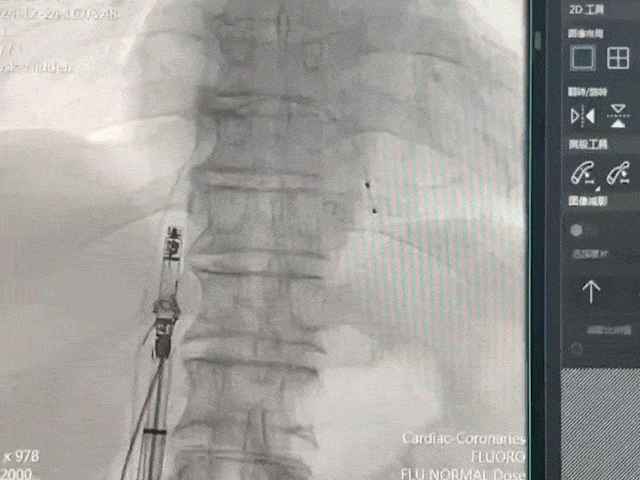

手术过程部分展示

将保护套筒送至下腔心房交界处

后撤保护套筒激活无导线起搏器,调至备用起搏模式